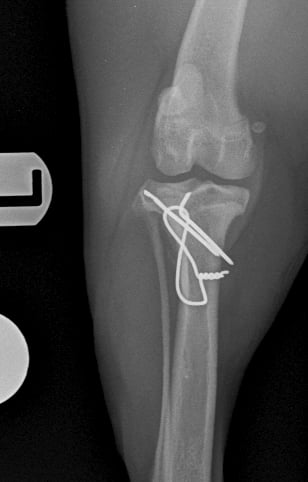

Surgical repair was performed using a medial approach to the proximal tibia. The avulsed tibial tuberosity fragment was identified, anatomically repositioned, and stabilized with two 1.2 mm Kirschner pins and a 1 mm tension band wire (Figs. 3 and 4).

Fig. 3